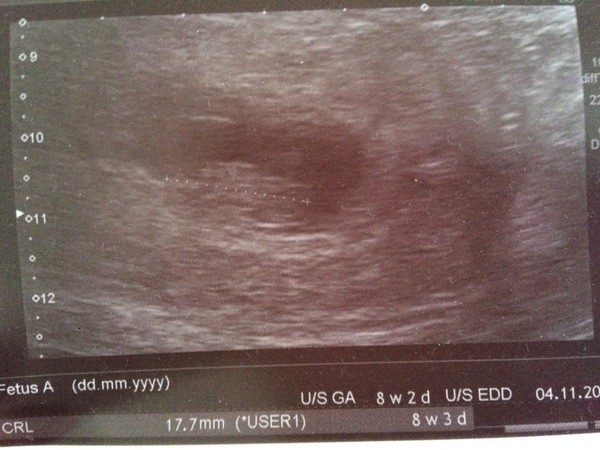

TheImprobableGirl · 02/04/2018 11:44

This is my scan photo.... I was a bit Hmm at the fuzzy grey blob - but I think there was a miscommunication and i should have been sent to early pregnancy rather than the antenatal clinic!